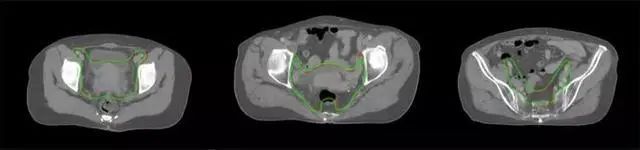

四、放射治療智能勾畫軟件

產(chǎn)品背景

放射治療,簡稱放療,是治療腫瘤主要手段之一,利用放射線破壞照射區(qū)(靶區(qū))的細(xì)胞,使腫瘤細(xì)胞停止分裂直至死亡,醫(yī)生通常把放射治療形象的比喻為“打靶”,放療前精準(zhǔn)勾畫腫瘤靶區(qū)范圍是腫瘤放射治療的關(guān)鍵步驟。傳統(tǒng)的靶區(qū)勾畫醫(yī)生會根據(jù)患者多張CT、MRI影像片憑借經(jīng)驗進(jìn)行,比較耗時,治療的病人數(shù)量也有限,且靶區(qū)勾畫缺少行業(yè)統(tǒng)一的規(guī)范和標(biāo)準(zhǔn),無法達(dá)到同質(zhì)化,勾畫精確度不理想。

技術(shù)原理

基于深度學(xué)習(xí)人工智能的放療靶區(qū)智能勾畫技術(shù)和自動計劃技術(shù),基于全面的市場調(diào)研和臨床專業(yè)意見,采用獨創(chuàng)的基于小樣本量的人工智能算法,實現(xiàn)放療靶區(qū)和危及器官的快速全自動勾畫。

產(chǎn)品優(yōu)勢

縮短至幾分鐘內(nèi)便可完成,大幅提升了放療效率,且人工智能平臺完成的靶區(qū)勾畫可基本滿足臨床醫(yī)生需求,專家只需審核時細(xì)微調(diào)整,可顯著提高靶區(qū)勾畫的規(guī)范化及精準(zhǔn)度,讓放療智能化,標(biāo)準(zhǔn)化??筛采w食管癌、鼻咽癌、直腸癌、宮頸癌、肺癌等多種病種。